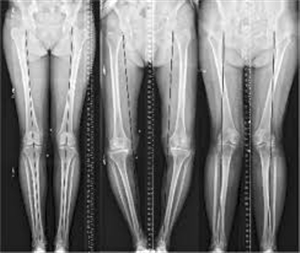

Phục Hồi Trục Chi

Phục hồi trục chi: yếu tố quan trọng của các phẫu thuật điều trị thoái hoá khớp gối Phẫu thuật thay khớp gối được biết đến như là phương pháp điều trị có hiệu quả cho các trường hợp tổn thương thoái hoá khớp gối nặng. Tuy nhiên còn 2 phương pháp phẫu thuật nữa […]